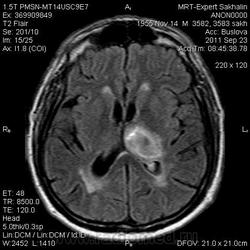

ID:53258

Онмк по геморрагичесому типу с образованием внутримозговой гематомы (подострая аза), прорывом в полость левого бокового и III -го желудочков.

Для чего введен контраст, какая цель преследовалась?

Цель введения контраста наверное для исключения объема. Хотя. Наверное только динамика ответить на данный момент. Надо выносить в заключение весь диагностической ряд. Но больше похоже действительно на зона геморрагического НК. А сосуды не делали? Может имеет место венозное нарушение?